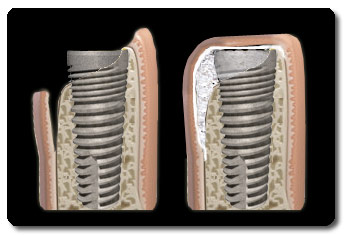

Botherstel procedure - Guided Bone Regeneration

In de bovenste afbeelding is te zien dat een deel van de schroef van het implantaat aan de linkerkant niet bedekt is met bot. Na het plaatsen van het implantaat zal de implantoloog het gebied waar te weinig bot is opvullen en bedekken met een soort van 'velletje', wat een membraan wordt genoemd. Het membraan schermt het nieuw te vormen bot af voor voor de sneller delende bindweefselcellen van het tandvlees. Het materiaal onder het membraan kan o.a. lichaamseigen bot zijn, maar ook donorbot, kunstbot of runderbot. Naar gelang de situatie en de hoeveelheid benodigd bot, zal er één van of een combinatie van de eerder genoemde materialen gebruikt worden. Deze techniek wordt Guided Bone Regeneration genoemd (GBR).

In de bovenstaande afbeelding is na het plaatsen van het implantaat een gedeelte niet bedekt door bot. Het botdefect wordt opgevuld met (kunst)bot en bedekt met een membraan. Hoewel niet afgebeeld, zal het tandvlees hier weer overheen gehecht worden en zal het lichaam over het algemeen drie tot zes maanden nodig hebben om voldoende nieuw bot te vormen.